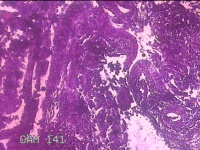

宫颈内容物

性别

女

年龄

29岁

临床诊断

异常子宫出血

一般病史

不规则阴道流血1个月余。

标本名称

大体所见

灰白暗红色不规则碎组织1.8x1.3x0.3cm一堆。

图3